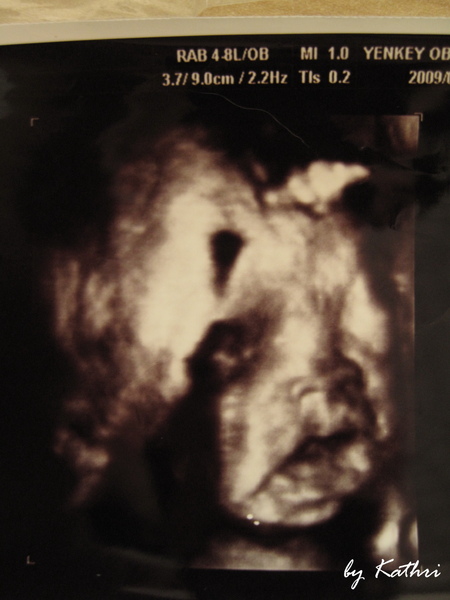

因為還在煩惱到底要用什麼方法讓何必呢出來,所以為了以防萬一,還是想說找個家裡附近的婦產科比較好,如果說喜歡,那到時候如果決定是要自然產,就可以不要跑得太遠,免得到時候窮緊張。

鄰居推薦了他生小朋友的那家診所,離我們家騎車大概十幾分鐘就到了,老公yahoo了一下他,評價也不錯,所以我們就去了,結果誤打誤撞的幫何必呢拍到了4D的照片。